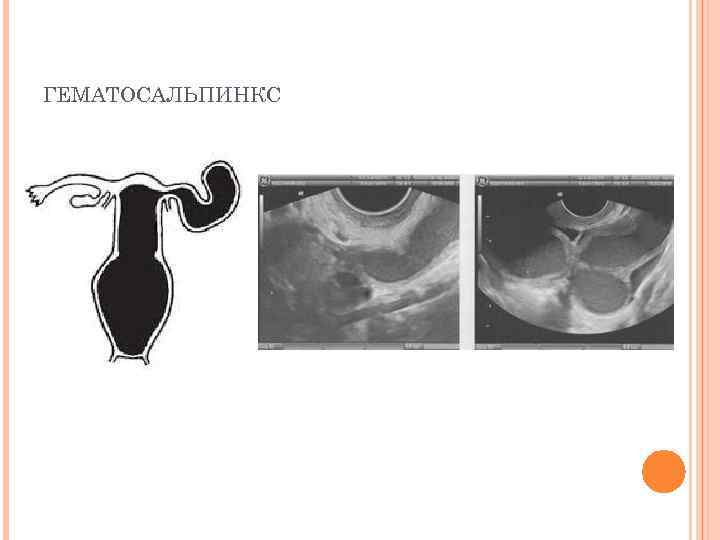

ХАРАКТЕРИСТИКА ЗАБОЛЕВАНИЯ Проявлениями атрезии влагалища могут считаться Ø накопление менструальной крови в вагинальном своде (гематокольпос), накопление крови в полости матки (гематометра), накопление крови в фаллопиевой трубе (гематосальпинкс), накопление слизи в вагине (мукокольпос) а также невозможность или ограничения полового сношения. Ø Ø

ГЕМАТОСАЛЬПИНКС

ДИАГНОСТИКА АТРЕЗИИ ВЛАГАЛИЩА Гинекологический осмотр – позволяет разглядеть в половом отверстии куполообразно выделяющийся гематокольпос; Ректо-абдоминальное исследование – показывает высокое расположение увеличенной матки, и при атрезии вагины позволяет обнаружить высоко размещенную, увеличенную матку и трубы. Органы отечны и резко болезненны; Зондирование - определяет глубину вагинального свода и степень патологии. Обычно этот метод используют непосредственно перед хирургической коррекцией влагалища; Бактериологическое и микроскопическое исследование мазка – показывает наличие патогенной флоры в половых органах; Ультразвуковая диагностика (УЗИ) - выявляет наличие, расположение и размеры патологических образований. Особенно хорошо показывает гематометру (пиометру) и гематосальпинкс (пиосальпинкс); Томография органов малого таза (МРТ) – позволяет определить гематокольпос маленького размера; Диагностическая лапароскопия - также успешно применяется для диагностики атрезии; Вагинография - введение контрастного вещества с последующим рентгенографическим исследованием выше зоны поражения. Также дает хорошие результаты. Урологическое обследование – показано при затрудненном оттоке мочи при наличии свищевого пиокольпоса.